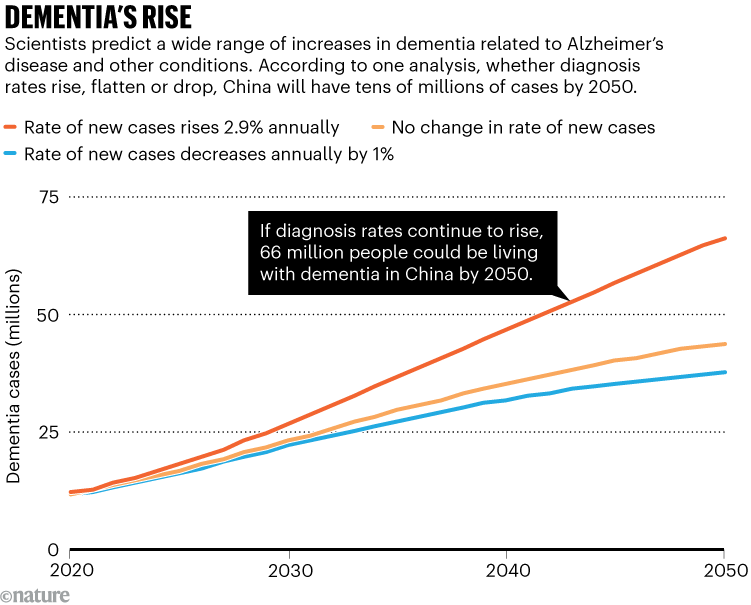

Treating the root of the problem

Nearly 17 million people in China had Alzheimer’s disease and related dementias in 2021 — about 9 in 1,000, according to a report published last year1. Projections suggest that this number could reach as high as 66 million by 2050 (see ‘Dementia’s rise’) or even exceed 100 million by then2,3. The problem is compounded by China’s low fertility rate, which means that there will be fewer people of working age to support the growing population of older individuals with debilitating conditions.

Source: Ref. 2